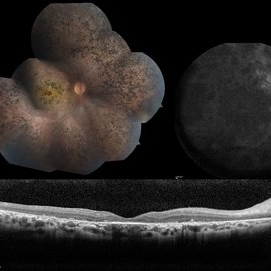

LCA type 10 due to mutations in CEP290. 36-year-old male with best corrected visual acuity of light perception in both eyes since childhood. On color fundus imaging, there is a mix of polymorphous white flecks and pigmentary changes. On autofluorescence imaging, there is almost complete loss of macular RPE. On OCT, there is complete loss of inner and outer retinal layers, the greatest losses occurring centrally.

Photographer: Stephen Tsang, MD, PhD

Condition/keywords: Leber Congenital Amaurosis